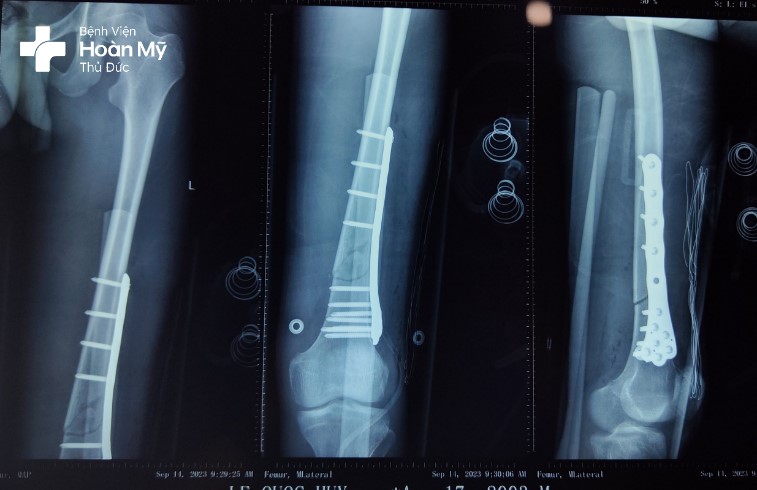

X-quang đùi trái trước mổ gãy 1/3 dưới thân xương đùi trái di lệch nhiều

Hình chụp X-quang sau mổ: kết hợp xương nẹp vít